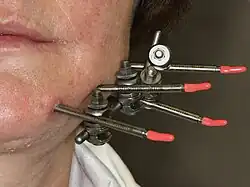

Closed reduction with direct skeletal fixation follows the same premise as MMF except that wires are passed through the skin and around the bottom jaw in the mandibule and through the piriform rim or zygomatic buttresses of the maxilla then joined to secure the jaws. The option is sometimes used when a patient is edentulous (has no teeth) and rigid internal fixation cannot be used.

Open reduction with direct skeletal fixation allows the bones to be directly mandibulated through an incision so that the fractured ends meet, then they can be secured together either rigidly (with screws or plates and screws) or non-rigidly (with transosseous wires). There are a multitude of various plate and screw combinations including compression plates, non-compression plates, lag-screws, mini-plates and biodegradable plates.

External fixation, which can be used with either open or closed reduction uses a pin system, where long screws are passed through the skin and into either side of a fracture segment (typically 2 pins per side) then secured in place using an external fixator. This is a more common approach when the bone is heavily comminuted (shattered into small pieces, for instance in a bullet wound) and when the bone is infected (osteomyelitis).

External fixation of left mandible fracture

External fixation of left mandible fracture

High velocity injuries

In high velocity injuries, the soft tissue can be severely damaged far from the bullet wound itself due to hydrostatic shock. Because of this the airway must be carefully managed and vessels well examined. Because the jaw can be highly comminuted, MMF and rigid internal fixation can be difficult. Instead, external fixation is often used[33],.[34]